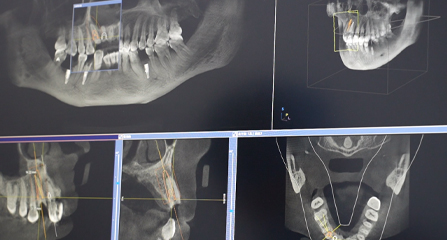

先进设备是口腔医院为市民提供高效诊疗服务的根本,茀莱堡口腔医院不断升级口腔诊疗设备,采用国际先进口腔治疗理念。全套引进德国西诺德CBCT全景片、可视导航种植系统、iTero 口扫、无痛舒适麻醉仪等一系列先进的口腔医疗设备,实现口腔医疗的全数字化;确保口腔诊疗更加严谨、精密和安全。

• 三维影像数据 一次性精确采集

三维影像数据 一次性精确采集